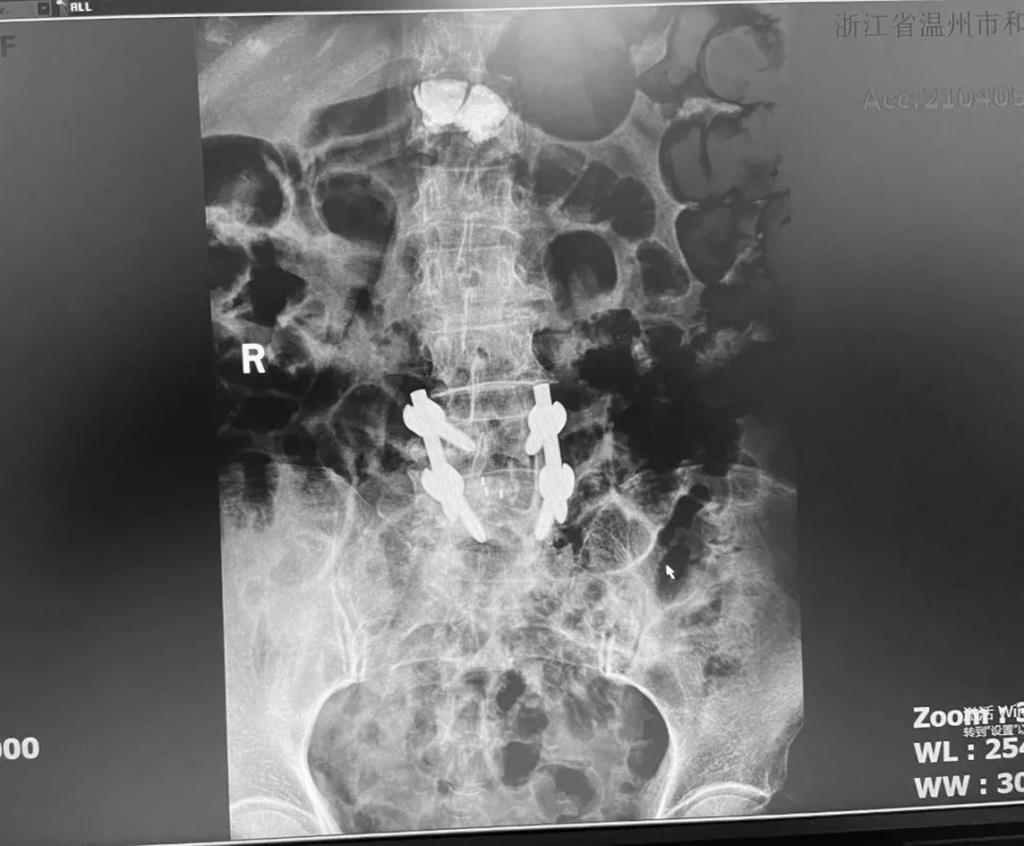

據(jù)了解,脊柱內(nèi)鏡下腰椎融合術(shù)只需要打幾個(gè)“鑰匙孔”即可完成。聽(tīng)起來(lái)是不是很簡(jiǎn)單?在脊柱內(nèi)鏡下,劉丹主任先后為患者進(jìn)行了椎管減壓、椎間盤(pán)摘除,再實(shí)施椎弓根螺釘放置、椎體植骨融合內(nèi)固定,一系列步驟有條不紊。

看似簡(jiǎn)單的幾個(gè)步驟,但實(shí)際上很復(fù)雜,需要主刀醫(yī)生有豐富的手術(shù)經(jīng)驗(yàn)和細(xì)致耐心的操作。

術(shù)中只需切開(kāi)4個(gè)如“鑰匙孔”般大小的孔道